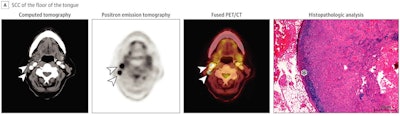

"In this cohort of 135 patients with newly diagnosed SCC of the oral cavity, FDG-PET/CT was able to detect the primary tumor in 97.8% of the cases, thereby confirming the high sensitivity of FDG-PET/CT and its superiority to stand-alone CT and MRI," stated the authors, led by Dr. Christian Linz, PhD, of the University Hospital of Würzburg, Germany.

The accuracy of FDG-PET/CT in localizing primary tumor, lymph node, and distant metastases was tested and compared against histopathologic characteristics of tissue samples. Two experienced, board-certified nuclear medicine physicians with access to relevant clinical data independently rated the whole-body and cervical PET/CT imaging results.

Results showed 83.3% sensitivity, 84.8% specificity, and a negative predictive value of 93.3% with use of FDG-PET/CT imaging for detecting cervical lymph node metastases. In addition, in 125 patients of the study cohort, measures were also compared with morphologic imaging via MRI and contrast-enhanced CT. The researchers found FDG-PET/CT's specificity was significantly higher than that observed in cervical MRI and CT.